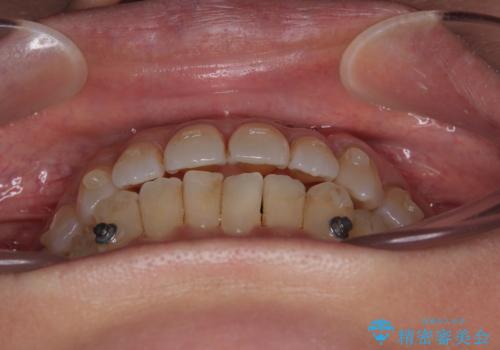

受け口と八重歯を改善 インビザライン矯正治療

- 前歯のデコボコや八重歯を治したいとのことで来院された患者様です。

受け口傾向の骨格であり、前歯はクロスバイトまたは切端咬合となっており、下顎を中心に歯列全体の後方移動を行い、IPR(歯と歯の間を削る)によってデコボコが解消するように設計し、インビザラインにより治療を行うこととしました。

受け口傾向のインビザライン矯正は比較的治療を行いやすいため、きれいに仕上げることができました。舌の突出癖が顕著であったため、改善のためのトレーニングをしっかりと行っていただきました。